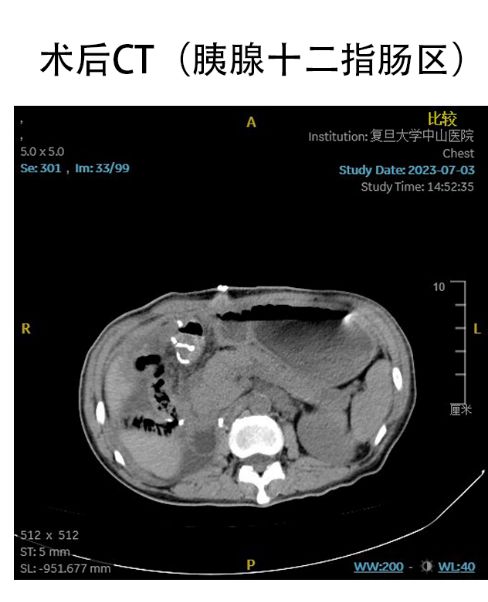

然而曾女士的腹盆腔增強CT結(jié)果提示,腫瘤向上包繞胰腺、十二指腸和小腸系膜,向下生長至盆底壓迫直腸,向后完整包繞右側(cè)腎臟以及腹腔大血管,向前從腹壁膨出形成腹壁疝,占據(jù)了其整個腹腔!

6月23日,經(jīng)過周密的術(shù)前準備,張勇主任與童漢興副主任醫(yī)師、王炯元主治醫(yī)師在5個小時內(nèi),在復(fù)雜粘連和因腫瘤推擠而異位的臟器中精準分離出胰腺、十二指腸、小腸結(jié)腸及其系膜、左側(cè)腎臟、膀胱和子宮,保護了腸系膜上血管、輸尿管、腹主動脈、下腔靜脈和股神經(jīng)等關(guān)鍵結(jié)構(gòu),完整切除了腹膜后巨大腫瘤以及右側(cè)腎臟、部分小腸、左半結(jié)腸、直腸、右側(cè)附件。充分考慮術(shù)后可能出現(xiàn)的淋巴瘺、出血、腸瘺、循環(huán)衰減等術(shù)后并發(fā)癥,專家團隊還為患者進行了全面、細致的術(shù)后水電解質(zhì)平穩(wěn)維持、循環(huán)呼吸監(jiān)護、腸內(nèi)外營養(yǎng)支持等管理。術(shù)后第一天,曾女士的腹脹和呼吸急促癥狀顯著改善。7月18日,曾女士恢復(fù)良好,順利出院。